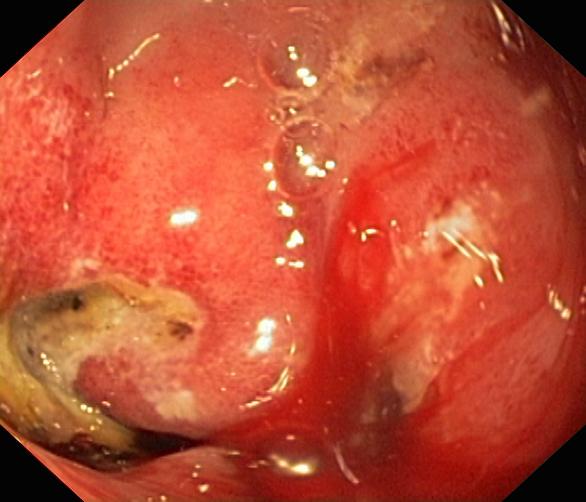

Krwawienie

Wrzód trawienny